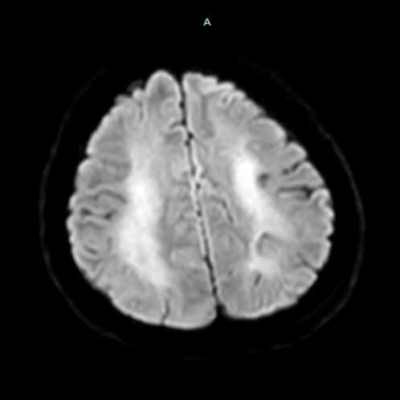

- A) Bilateral serebral kortekste (oklar) ve bazal ganglionlarda (oklar) yaygın DAG hiperintens, ADC hipointens difüzyon kısıtlamaları görülüyor.

- B) 9 gün sonraki difüzyon MR incelemede kortikal ve bazal ganglionlardaki difüzyon kısıtlamalarının gerilediği, bilateral serebral beyaz cevherde (oklar) ve internal kapsül arka bacağı- kortikospinal trakt boyunca (oklar) yaygın DAG hiperintens, ADC hipointens difüzyon kısıtlamalarının geliştiği izleniyor.